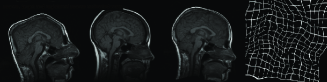

In Figure 9, three example registration results of randomly and nonlinearly warped images are shown. Capturing signal intensity variations during registration process with intensity standardization method leads to assesment of visual comparision of registered source and target images with warping grid. Evaluation of the registration results is summarized in Table-2. The table shows that large and small scale deformations are captured accurately on the standard intensity scale. Resulting images have fixed intensity meanings even there is large intensity variations initially.

Figure 9: Resulting registration of images with random nonlinear warps. Each row includes source, target, registered source and estimated warping grid

Another method to evaluate proposed registration method is visual examination of checkerboard images. Figure 10 shows an elastic registration example together with checkerboard image illustrating how well the image pair is registered. Checkerboard image includes white and black squares corresponding to intensity values taken from the registered source and the target image respectively. Our overall observation from experimental results is that multiresolution elastic registration on standard intensity scale can capture both local and global deformations with high accuracy.

Figure 10: First row includes the source and target images, second row shows registered source with warped grid and checkerboard image for visual assesment